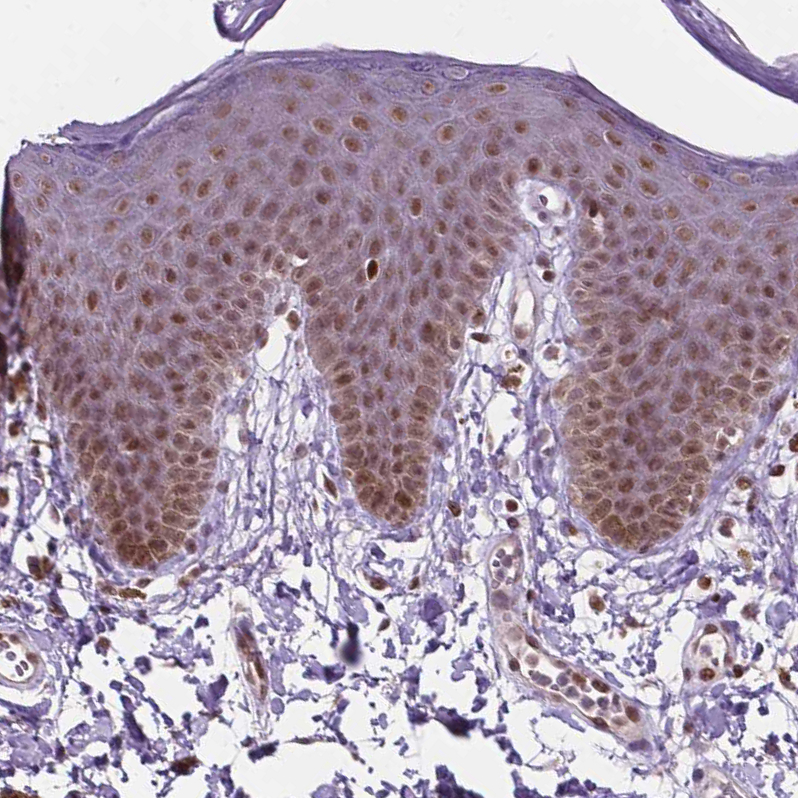

Immunohistochemical staining of human skin shows moderate nuclear positivity in squamous epithelial cells.